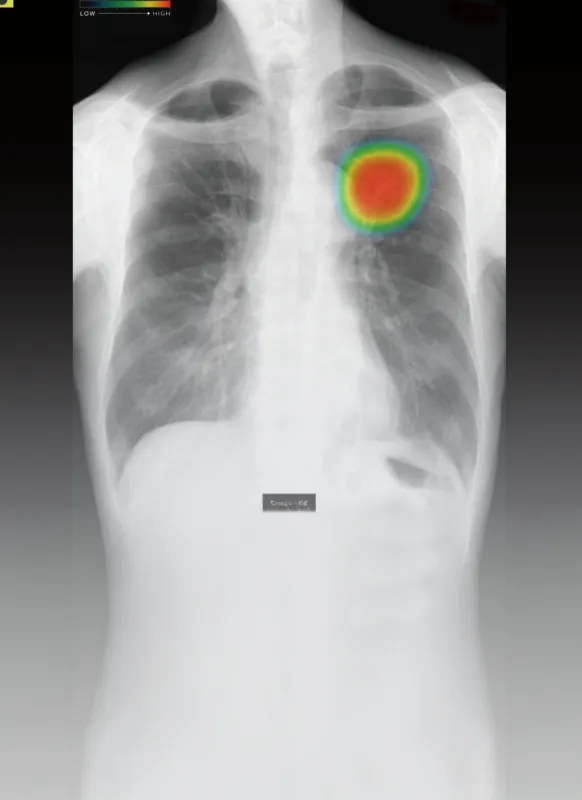

AIによる胸部X線画像解析をはじめとした先端技術を積極的に導入し、診断の精度向上と早期発見に努めています。また、院内には高性能空気清浄装置を設置し、清潔で快適な診療環境を整備。常に新しい医療技術や設備を取り入れることで、患者さまにとって安心・安全で質の高い医療を提供し続けています。